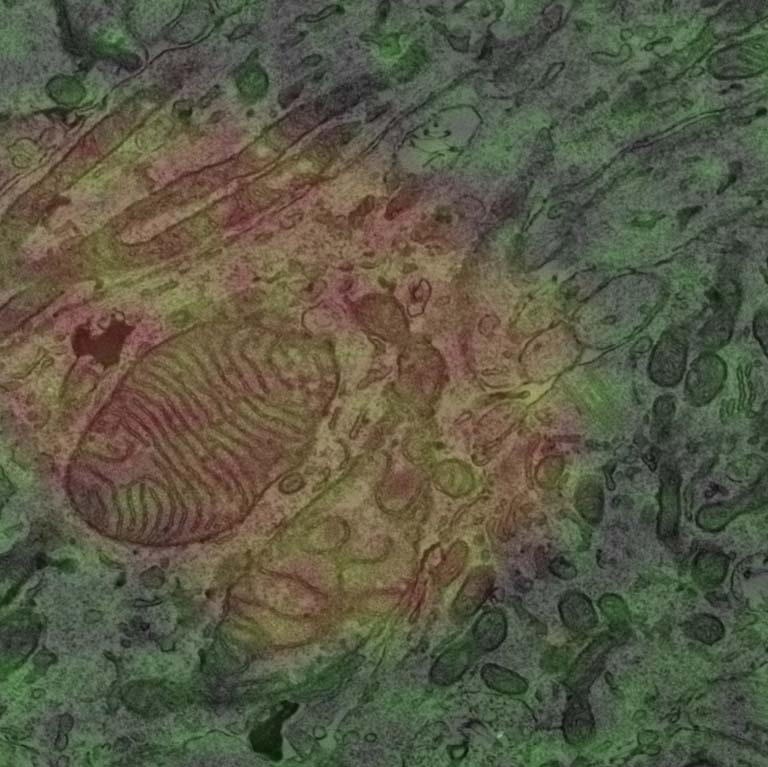

Using human stem cells, we made mini brains to study how Rett Syndrome, a neurodevelopmental disease, develops in the brain. We wanted to look closely at mitochondria to see if there are any differences due to the disease. However, the tissue is very dense, so we tried a method to label different cells in the brain. Neurons were labeled in green and glia were labeled red. We fluorescently imaged the mini brains, then did super-resolution electron microscopy (EM) imaging. After, the fluorescent images were overlayed onto the EM (Correlative Light Electron Microscopy) allowing us to look at the different cell types with high definition.

With this incredibly difficult technique, we were able to identify significant morphological defects in mitochondria between cell types in Rett Syndrome mini brains with high resolution.